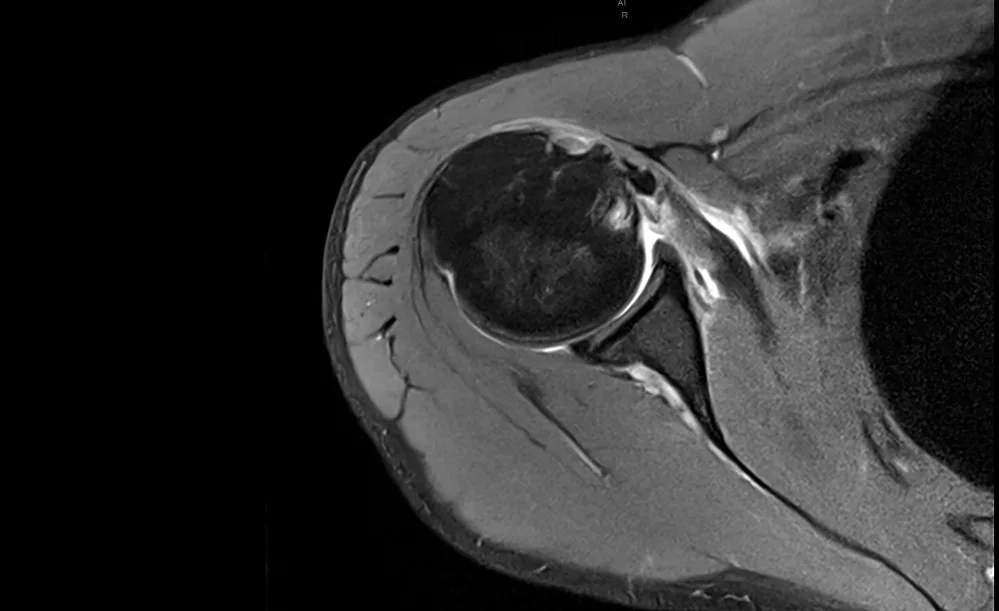

L’épaule est l’articulation la plus mobile du corps humain. Cette mobilité exceptionnelle, qui nous permet de projeter un bras vers l’arrière ou de porter la main vers le ciel, a cependant une contrepartie directe : une vulnérabilité accrue à l’instabilité. Lorsqu’une épaule se luxe une première fois, c’est-à-dire que la tête de l’humérus sort totalement de son logement (la glène), le risque de récidive devient une préoccupation majeure, particulièrement chez le sujet jeune et actif.

L’instabilité glénohumérale antérieure est l’une des lésions les plus courantes de l’épaule chez le sportif, notamment chez le joueur de rugby. Elle résulte d’une perte de la stabilité entre la tête de l’humérus et la glène de l’omoplate, provoquant des épisodes de luxation ou de subluxation.

Instabilité antérieure de l’épaule par le Dr Agout

L’épaule est l’articulation la plus mobile du corps humain ce qui lui permet des mouvements très amples. La contrepartie c’est que c’est aussi la plus instable, c’est à dire qu’elle peut se déboiter. L’instabilité, dans sa forme la plus spectaculaire, se traduit par une luxation, c’est à dire une perte de contact des surfaces articulaires entre l’humérus et l’omoplate.

L’instabilité de l’épaule par le Dr Agout

On parle de luxation lorsqu’on se déboite l’épaule. L’instabilité de l’épaule est une pathologie qui survient à la suite d’une luxation de l’épaule. L’articulation de votre épaule repose sur deux éléments : La Glène et l’Humérus. On parle de déboîtement de l’épaule lorsque la glène n’est plus en contact avec la tête de l’humérus.

L’épaule est l’articulation la plus mobile du corps humain, mais cette grande liberté de mouvement la rend également plus vulnérable aux luxations. La plupart des luxations (95%) se font vers l’avant, on parle de luxation gléno-humérale antérieure (entre la glène et l’humérus).